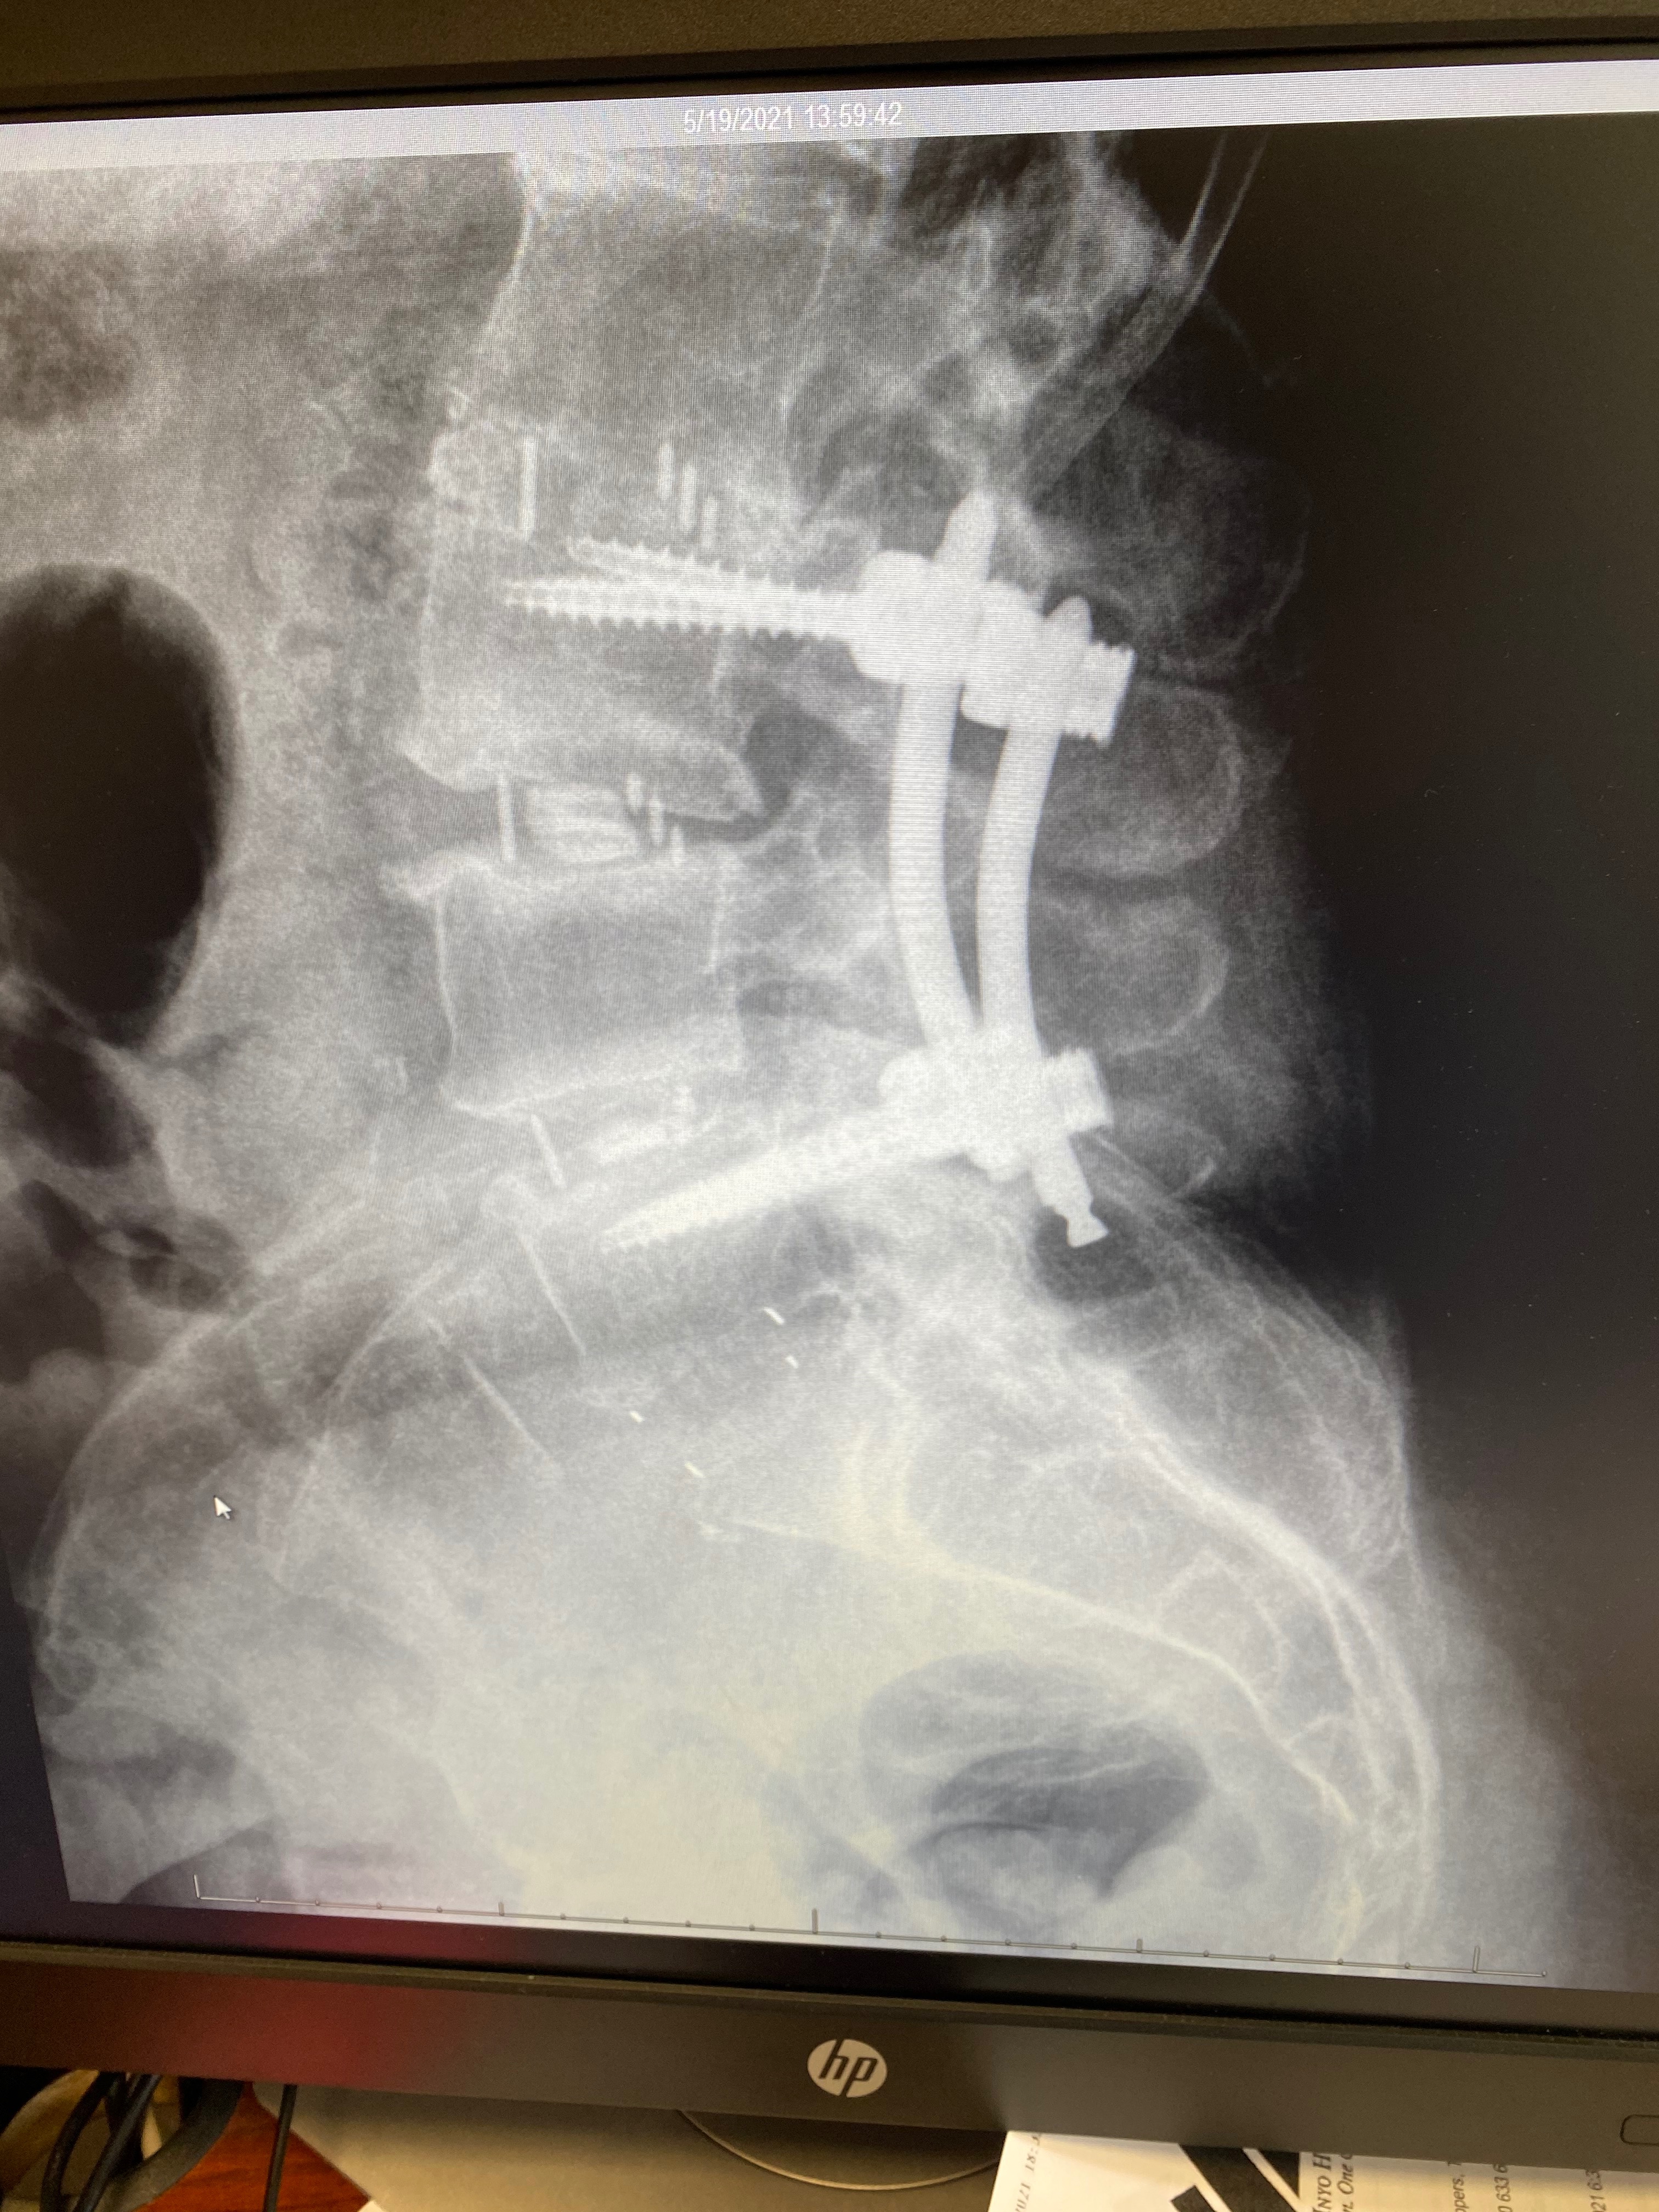

Lori has survived more surgeries than she can count but her hope remains strong. We are asking for your help to try one last treatment. Recent failed surgeries and setbacks have caused chronic pain leading to trouble walking with a cane. She has severe tears to her gluteus medius and minimus on her right hip, along with other bone and joint issues throughout her body. We found a top surgeon with a 90% success rate, but Medicare will not cover this treatment. Lori dreams of the day she can move without constant pain—not just for herself but for the animals who depend on her. Her greatest joy has always been caring for cats and dogs who need a second chance.

Lori’s double tendon reconstruction, is scheduled for January 22, 2026, where she will be in a hip and leg brace for 24/7 (except showers) for six weeks (she has been to this rodeo before with her surgery in January 2024 and this is the worst part of the recovery process), with thrice weekly physical therapy treatments. What makes Dr. Sanjum Samagh success rate 90% is his use of these three added procedures during surgery that we are asking for help with today. (Medicare will pay 100% of balance of surgery).